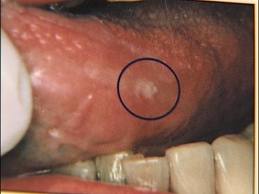

Other threats to older adults are the common cavity and oral infections, incidences of which increase with age. Lopez notes that cavities are a contagious disease influenced by many factors, including, dry mouth, side effects from medicine, Alzheimer's, dementia and other mental or physical disabilities, along with access to care. Bronchopneumonia and respiration of oral pathogens are other concerns. The bottom line is, bacterial infections of the mouth can spread throughout the body and contribute to overall health problems.